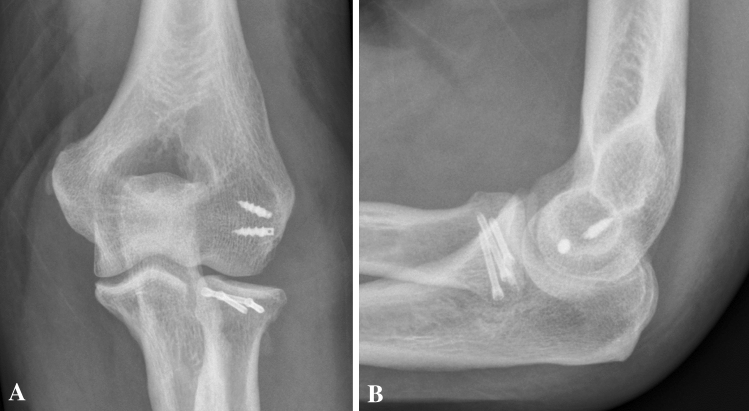

Fig. 6.

a, b Postoperative radiographs (lateral and anteroposterior) after radial head fixation with three CCS and reattached LCLC (Case 2). c and d after 6 months and metal removal